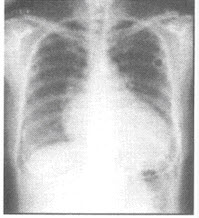

15、单项选择题

如图所示,左侧胸部病变,最可能的诊断为()

A.包裹性积液

B.恶性胸膜间皮瘤

C.左下肺脓肿

D.左下肺癌

E.左侧胸腔积液